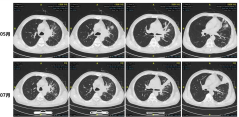

综合患者情况,建议继续口服伏立康唑抗感染,同时使用替吉奥抗肿瘤治疗。治疗后左肺病灶有所缩小,但左肺上叶气道狭窄明显。对于下一步抗肿瘤治疗方式,考虑到曲霉与肿瘤的平衡关系,以及患者肺部病灶局限在左肺门和左上肺,优先尝试局部放疗,并继续口服伏立康唑。放疗后病灶明显退缩,患者整体治疗较为成功,目前仍在持续随访中。